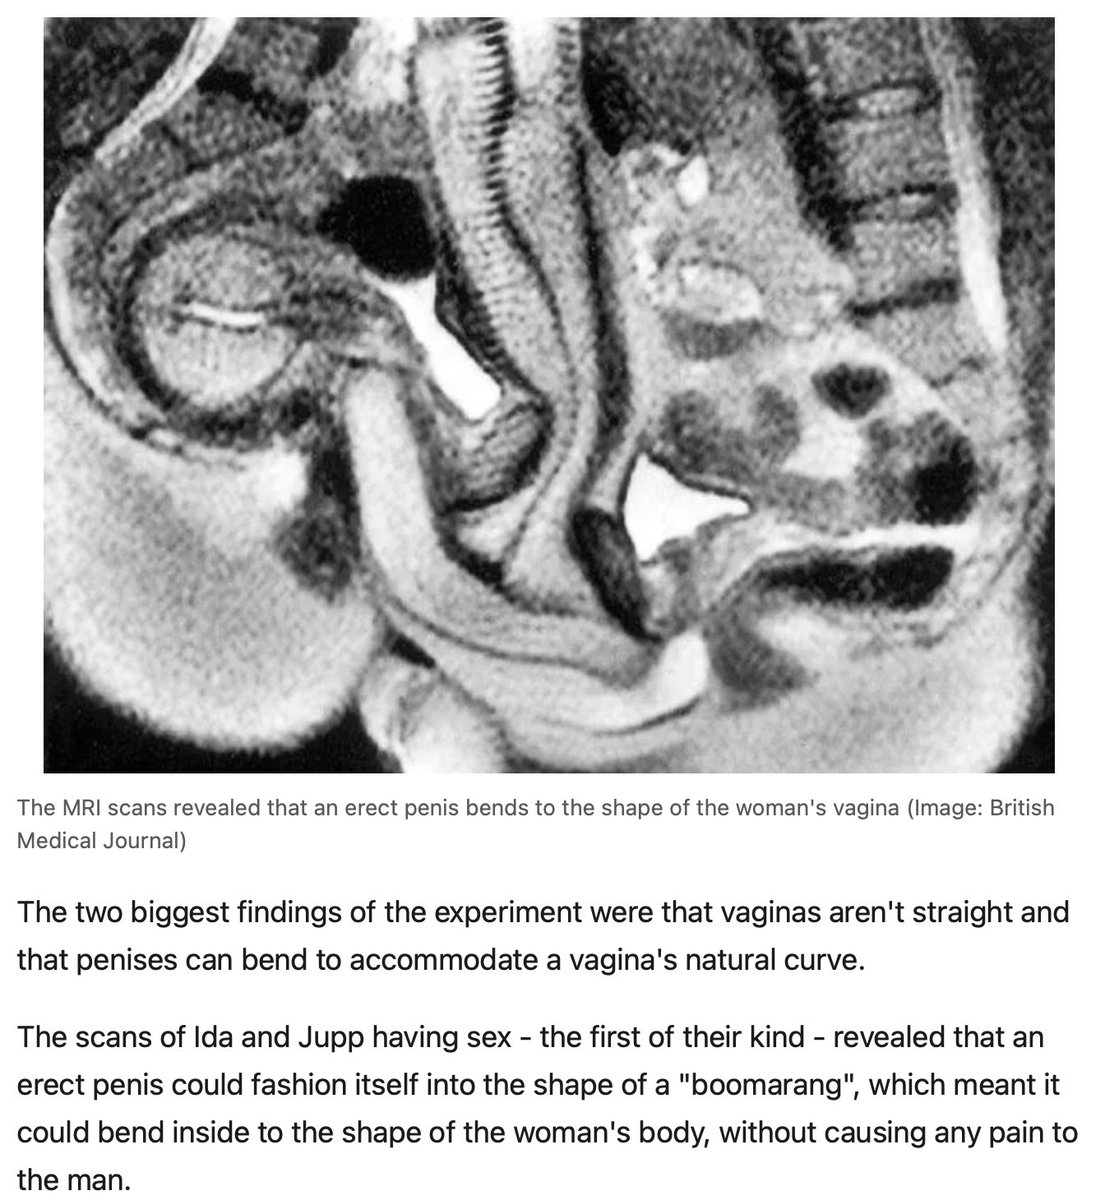

4. Both the penis and clitoris use different parts of the ANS system to perform physiologically but they both need to be programmed by photonics energy first. Once filled with photonic energy they lead to great sex as the picture below shows. The penis and clitoris are designed to be filled with blood as excitement grows. Blood is 93% water and suspended in it is a solar pigment called hemoglobin.